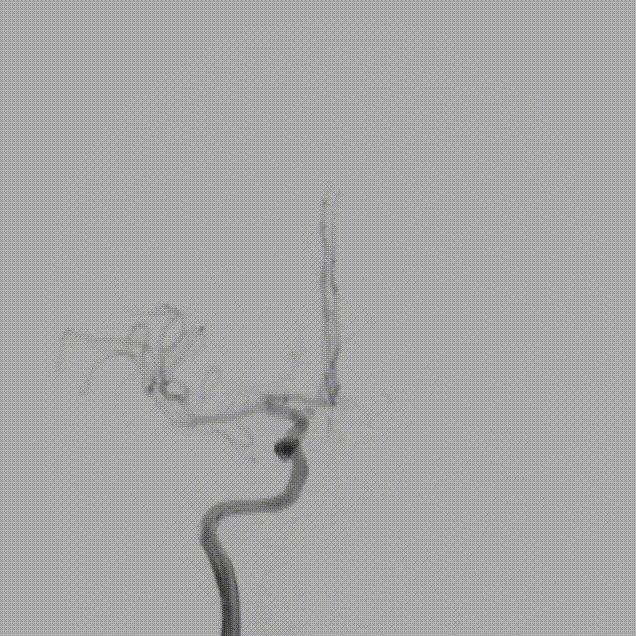

在泥鳅导丝及5F MPA1造影管配合下将6F股动脉长鞘至于左侧颈总动脉行路图,在200cm Sur-reach®微导丝配合下将2.5*15mm颅内球囊扩张导管扩张后,将6F导管鞘通过颈内动脉起始部闭塞段,行路图可见颈内动脉颈段至海绵窦段后膝处血栓影,左侧大脑中动脉闭塞。

将6F Oneering®远端通路导管自颈段负压抽吸至左侧大脑中动脉M1段,抽吸出大量血栓。行路图提示颈内动脉及大脑中动脉通畅。

术后造影:可见左侧颈内动脉通畅,大脑前动脉不显影,因患者前交通动脉开放,未处理。